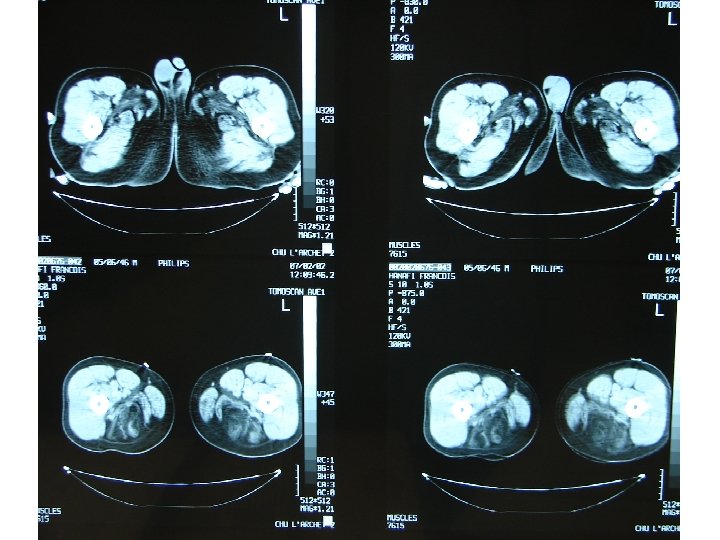

Démarche diagnostic: les examen complementaires Investigation à valeur d’orientation: - Imagerie (scanner, IRM musculaire) Complément indispensable de l’analyse clinique: dépistage atteinte infraclinique, cartographie muscles affectés, préalable à une biopsie IRM si suspicion d’une pathologie inflammatoire; dans les autres cas scanner !!! - Electromyogramme (EMG): Pour évaluer le caractère myogène, recher une myotonie, Stimulation répétitive pour recher une myasthénie etc.